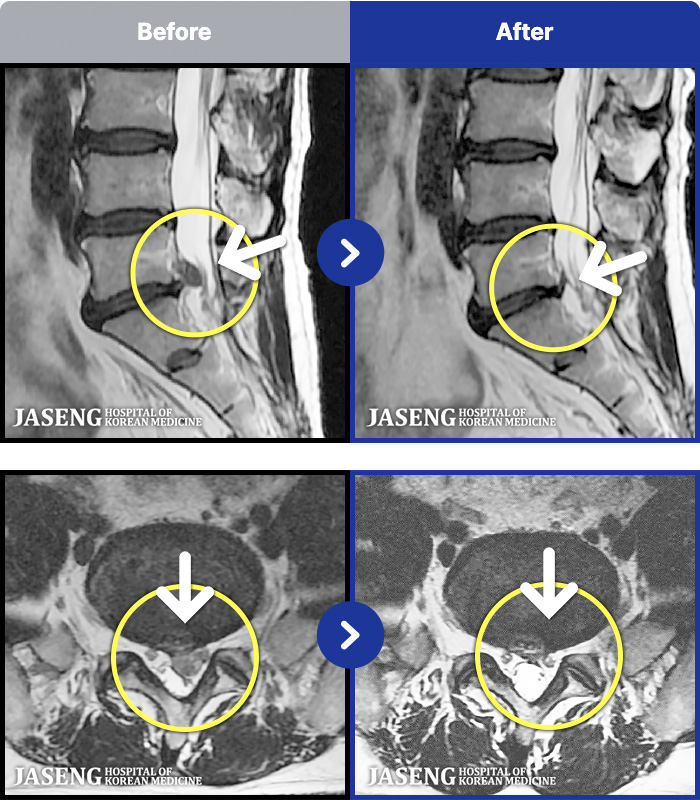

MRI ġ

63 MRI ũ ʸ Ȯϼ.

㸮 ϻ .

[Ȼ] 23.03.13~24.05.08

ȯںп Ǹ ǿ ԿǾ, ο ġ ۿ Ƿ ġḦ Ͻñ ٶϴ.

[Ȼ_㸮ũ] 㸮 ϻ .